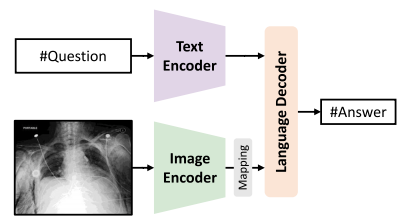

Fig. 14. Illustration of CLIP-driven methods for open-ended MedVQA

图14:由对比语言-图像预训练模型(CLIP)驱动的用于开放式医学视觉问答(MedVQA)方法的图示。